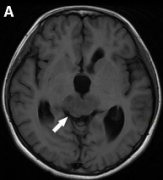

小儿颅内生殖细胞肿瘤亚型的MRI影像学特征

颅内生殖细胞瘤的组织学和位置不同,需要不同的临床治疗策略。我们的影像学特征可能有助于颅内生发瘤和非生发生殖细胞瘤(NGGCTs)的术前分化...